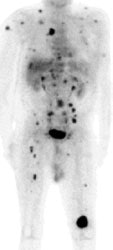

Widespread melanoma metastatses- PET alters patient management: The patient shown below was a 71 year old male with a history of melanoma on the left shoulder. A bone scan demonstrated the lesion in the left distal femur and also identified 4 spinal lesions. On CT, the abdomen had been interpreted as negative. The FDG PET exam revealed extensive metastatic disease throughout the body. The patient had been scheduled for tumor resection and total knee replacement surgery. After the PET exam the surgery was cancelled- avoiding both the cost and trauma of an ineffective operation. The exam was acquired on a Siemens ECAT EXACT PET scanner (manufactured by CTI). Case courtesy of Dr. Amjad Ali, M.D., Rush-Presbyterian-St. Luke's Medical Center, Chicago, IL and CTI PET Systems, Inc. |

Widespread melanoma metastatses- The case below is from a 53 year old male with metastatic melanoma. The exam demonstrates multiple soft tissue, lung, and osseous metastases. Note the larger field of imaging for the evaluation of metastatic melanoma which extends to below the knees. Some centers will perform whole body examinations in patients with melanoma. Note the faint gonadal activity and the markedly amount of activity within the distended urinary bladder. The exam was performed on an ECAT EXACT PET scanner (CTI) using a dose of 10.2 mCi FDG. Case courtesy of Oregon Positron Imaging, LLC, Albany, Oregon and CTI (The power behind PET). Click image to view cine avi file (230K) |